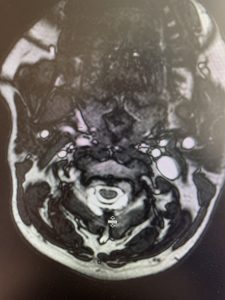

This 57 year-old male presents with severe neck, left shoulder and arm pain and weakness in his hand since being involved in a motor vehicle accident nine months prior. The patient had subsequent left shoulder surgery although he still complained of pain postoperatively and his weakness persisted. He was on no blood thinners. He underwent imaging. The cervical spine MRI revealed an extensive dorsal epidural collection from C1-2 through C5 with associated spinal cord compression. In addition there were multisegmental degenerative changes with foraminal stenosis worse at C4-5 (Fig. 1a and 1b).

(1a) Sagittal and axial T2-weighted cervical MRI demonstrating extensive dorsal epidural collection with hyperintense signal consistent with fluid causing spinal cord compression.